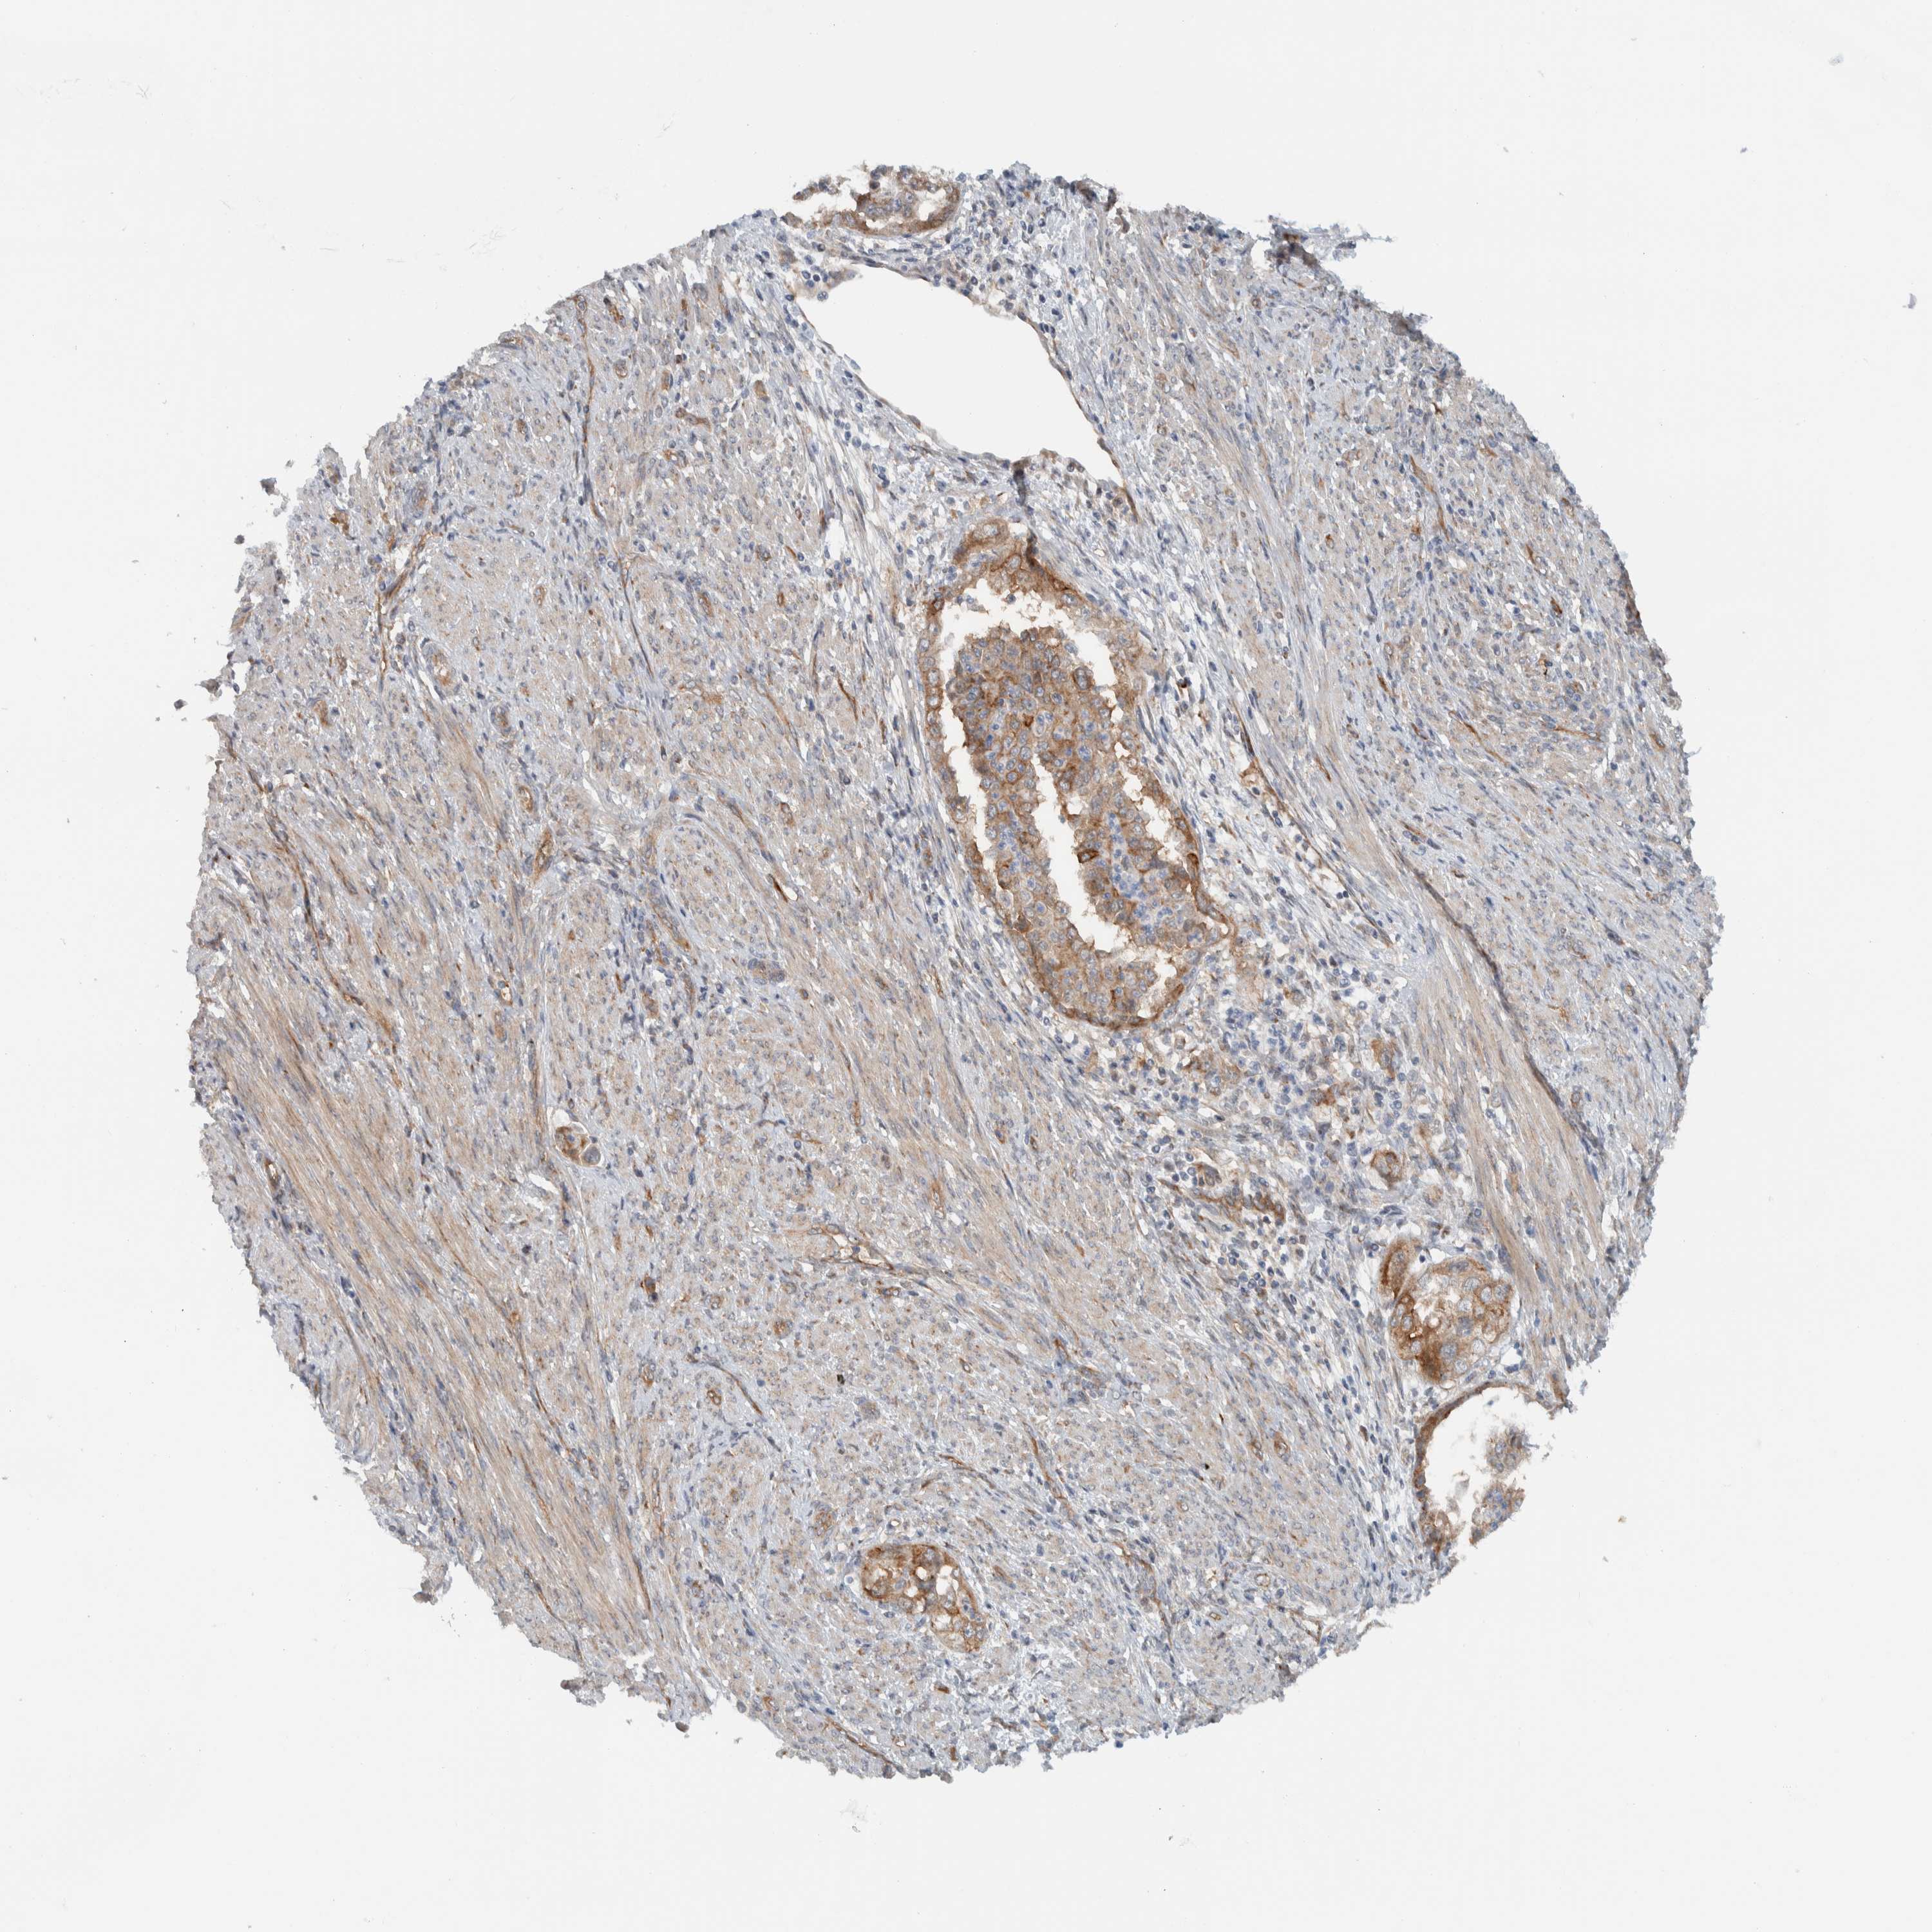

ENDOMETRIAL CANCER - Protein expressioni

A mouse-over function shows sample information and annotation data. Click on an image to view it in a full screen mode. Samples can be filtered based on level of antibody staining by selecting one or several of the following categories: high, medium, low and not detected. The assay and annotation is described here.

Note that samples used for immunohistochemistry by the Human Protein Atlas do not correspond to samples in the TCGA dataset.

Antibody stainingi

Antibody staining in the annotated cell types in the current human tissue is reported as not detected, low, medium, or high, based on conventional immunohistochemistry profiling in selected tissues. This score is based on the combination of the staining intensity and fraction of stained cells.

Each image is clickable and will lead to virtual microscopy that enables deeper exploration of all samples and also displays staining intensity scores, fraction scores and subcellular localization as well as patient and tissue information for each sample.

Antibody HPA024093

Staining

High

Medium

Low

Not detected

Intensity

Strong

Moderate

Weak

Negative

Quantity

>75%

75%-25%

<25%

None

Location

Nuclear

Cytoplasmic/membranous

Cytoplasmic/membranous,nuclear

Adenocarcinoma, NOS